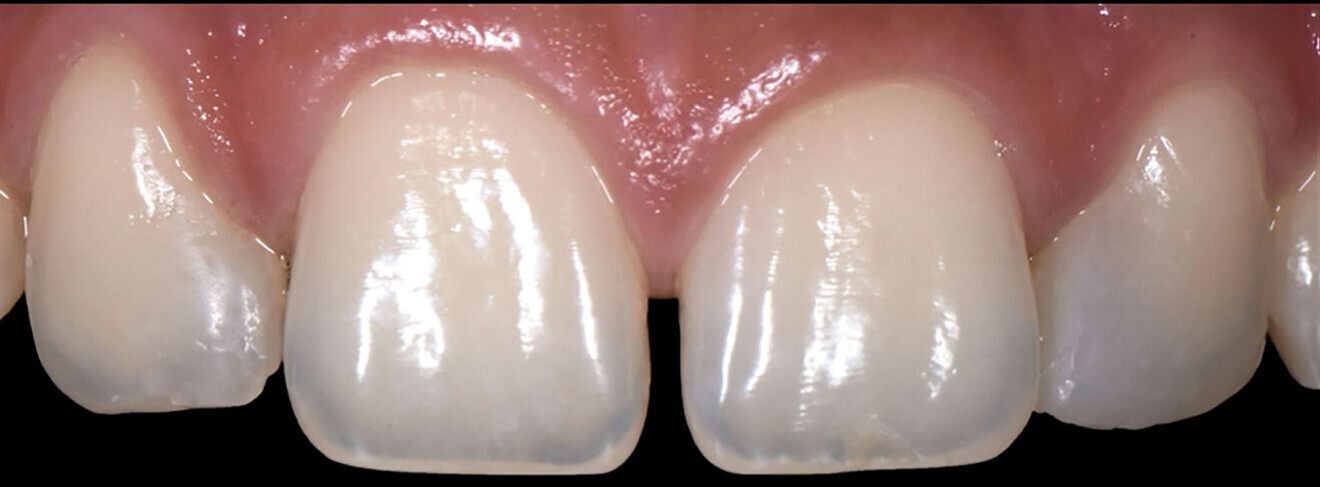

At the six-month follow-up appointment, the patient’s situation was very different to that at the initial consultation. There was proper closure of the interdental gaps and consequent formation of papillary tissue that harmonised the shape of the attached gingiva and of the reconstructed enamel perimeter (Figs. 18–21). In addition, the examination showed no fractures of the restoration or wear, no marginal discoloration or other staining, adequate marginal seal, adequate colour stability and translucency, very good surface structure and anatomical shape, excellent contact points, very good integrity of the teeth and no inflammation.

Fig. 20: Aesthetic result achieved.

Fig. 21a: Six-month follow-up.